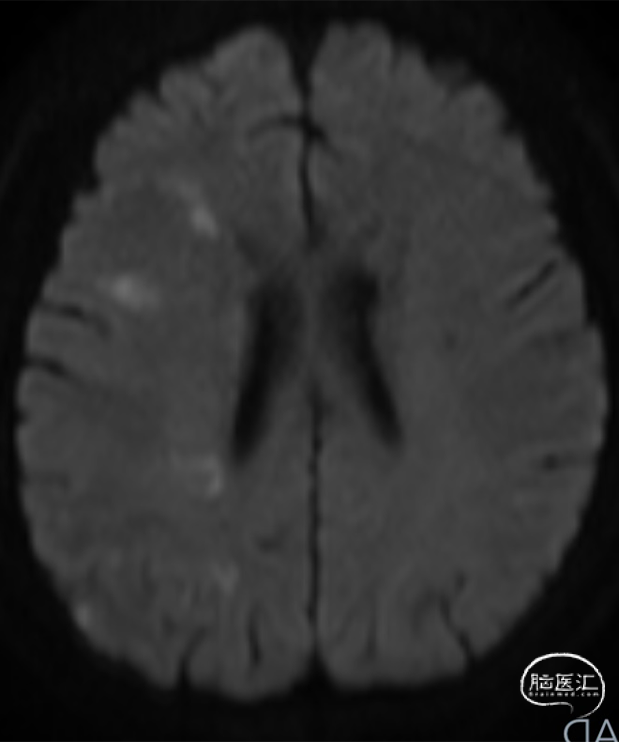

➤2024.3.20 头颅MRI

左侧基底节区/侧脑室旁及额顶枕叶急性期脑梗死。